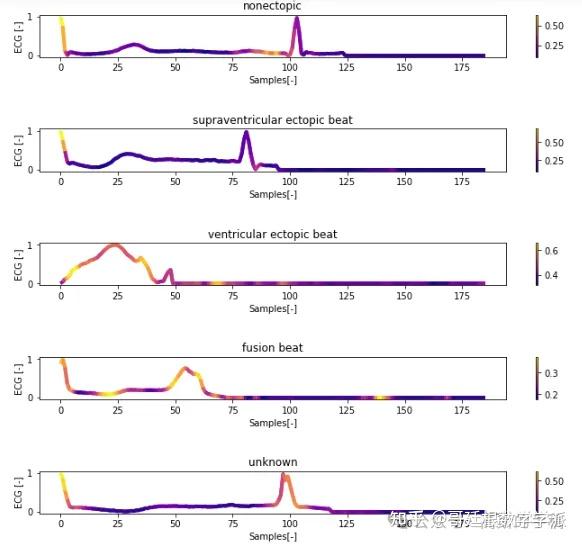

一维神经网络的特征可视化分析-以心电信号为例(Python,Jupyter Notebook)

包括Occlusion sensitivity方法,Saliency map方法,Grad-CAM方法